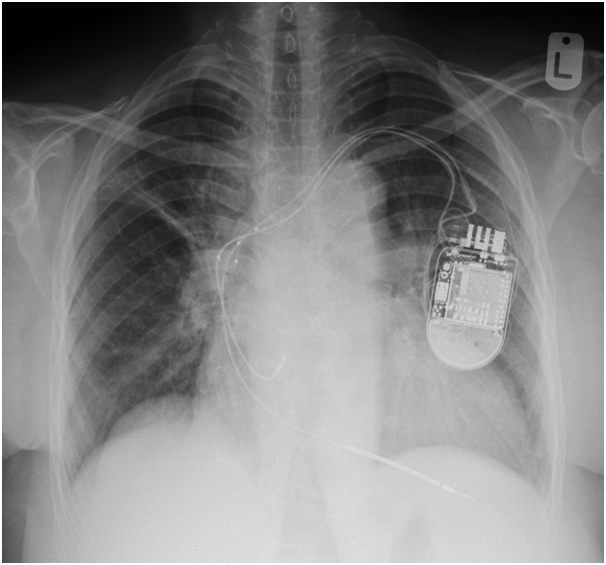

We were asked to see the patient, we reviewed her previous CXR post CRTD implantation and was (Figure 1) reviewed her procedure note which advocated the difficulty in securing LV lead deeply through lateral vein of the heart due to significant branch stenosis. The lead was then implanted in the posterolateral CS branch. Then, we requested a new CXR which showed the device slightly lower than implant position and displacement of LV lead higher in SVC (Figure 2).

Figure 2 The device slightly lower than implant position and displacement of LV lead higher in SVC.

Figure 5 Interrogation of CRTD with optimal results and normal post operative CXR.